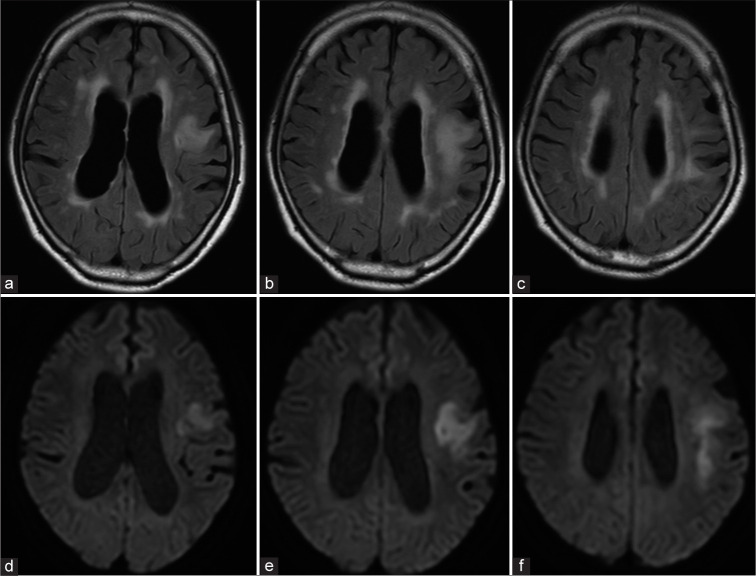

Progressive multifocal leukoencephalopathy associated with rituximab treatment.